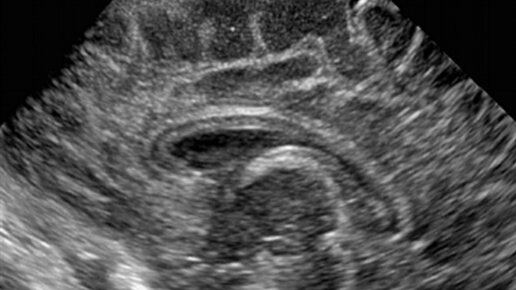

Головной и спинной мозг человека омываются защитным слоем цереброспинальной жидкости, или ликвора, который защищает центральную нервную систему, питает ее и отводит отработанные продукты обмена веществ. Ликвор циркулирует, поступая в полости внутри мозга - желудочки, и постоянно обновляется. Этот процесс начинается уже внутриутробно. У здорового плода с 15-й недели на узи можно увидеть боковые желудочки.  Во время рутинного ультразвукового исследования плода врач может обнаружить, что боковые желудочки в той или иной степени увеличены...